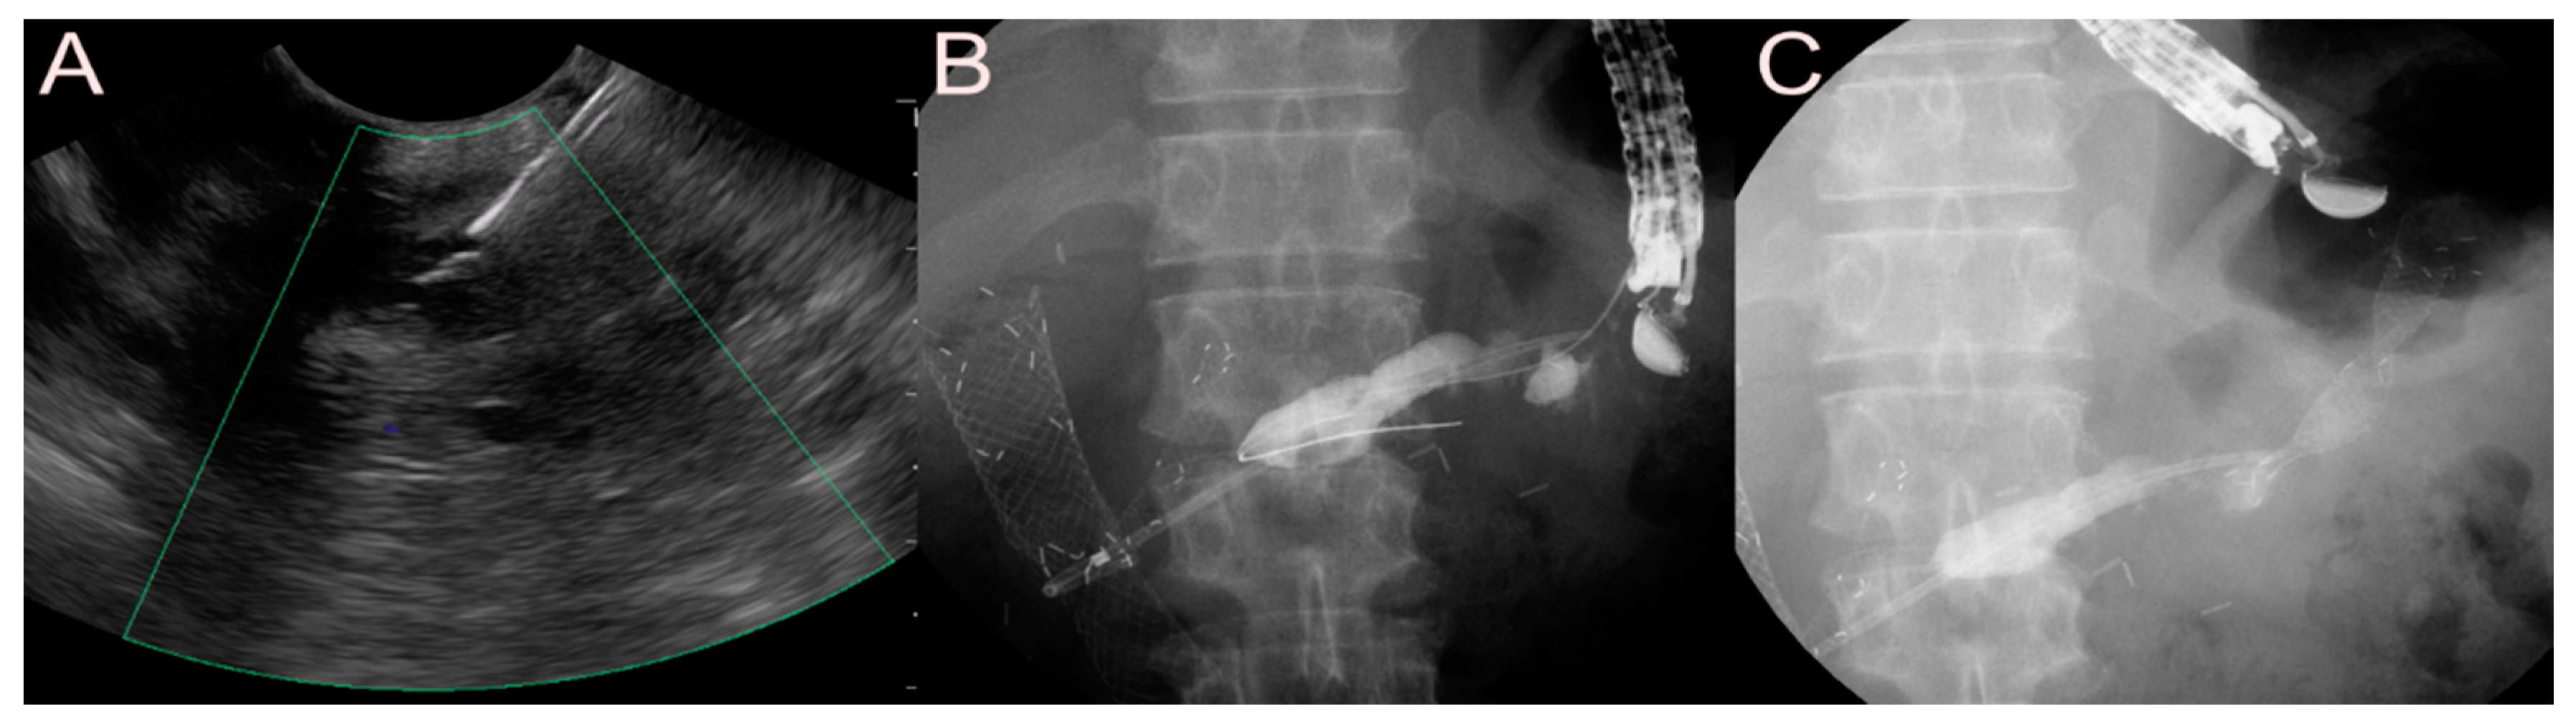

2.2.2. Use of the SEMS

2.2.3. Use of the LAMS